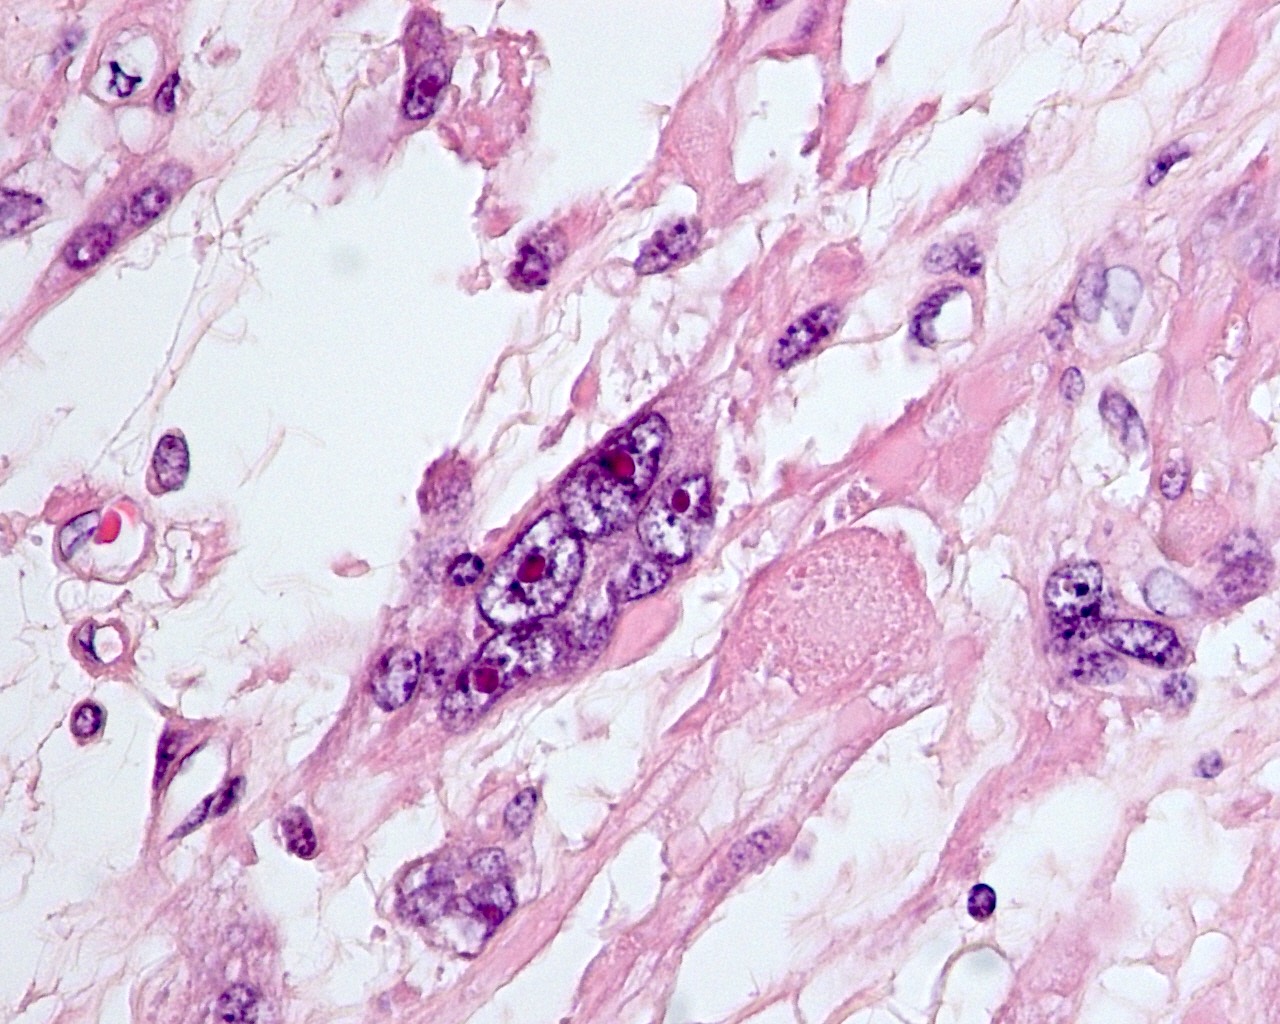

Webpathology.com: A Collection Of Surgical Pathology Images

uterus leiomyosarcoma myxoid webpathology multinucleated

leiomyosarcoma uterus myxoid pathology webpathology comments

leiomyosarcoma uterus myxoid pathology webpathology stroma comments